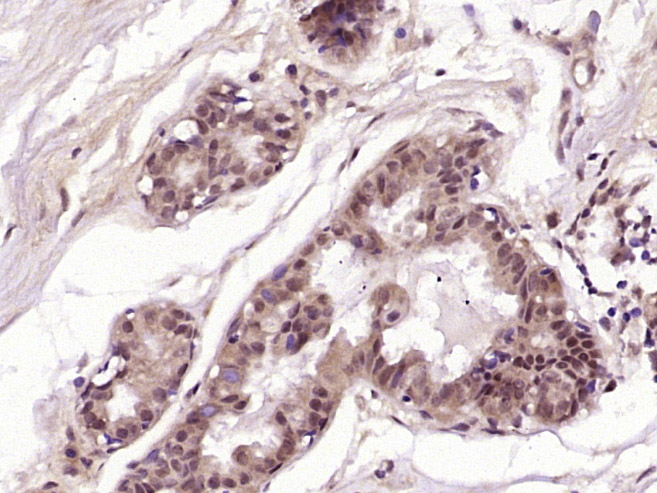

Paraformaldehyde-fixed, paraffin embedded (rat spleen); Antigen retrieval by boiling in sodium citrate buffer (pH6.0) for 15min; Block endogenous peroxidase by 3% hydrogen peroxide for 20 minutes; Blocking buffer (normal goat serum) at 37°C for 30min; Incubation with (PIBF1) Polyclonal Antibody, Unconjugated (bs-9612R) at 1:200 overnight at 4°C, followed by operating according to SP Kit(Rabbit) (sp-0023) instructionsand DAB staining.

Paraformaldehyde-fixed, paraffin embedded (human breast carcinoma); Antigen retrieval by boiling in sodium citrate buffer (pH6.0) for 15min; Block endogenous peroxidase by 3% hydrogen peroxide for 20 minutes; Blocking buffer (normal goat serum) at 37°C for 30min; Antibody incubation with (PIBF1) Polyclonal Antibody, Unconjugated (bs-9612R) at 1:400 overnight at 4°C, followed by operating according to SP Kit(Rabbit) (sp-0023) instructionsand DAB staining.